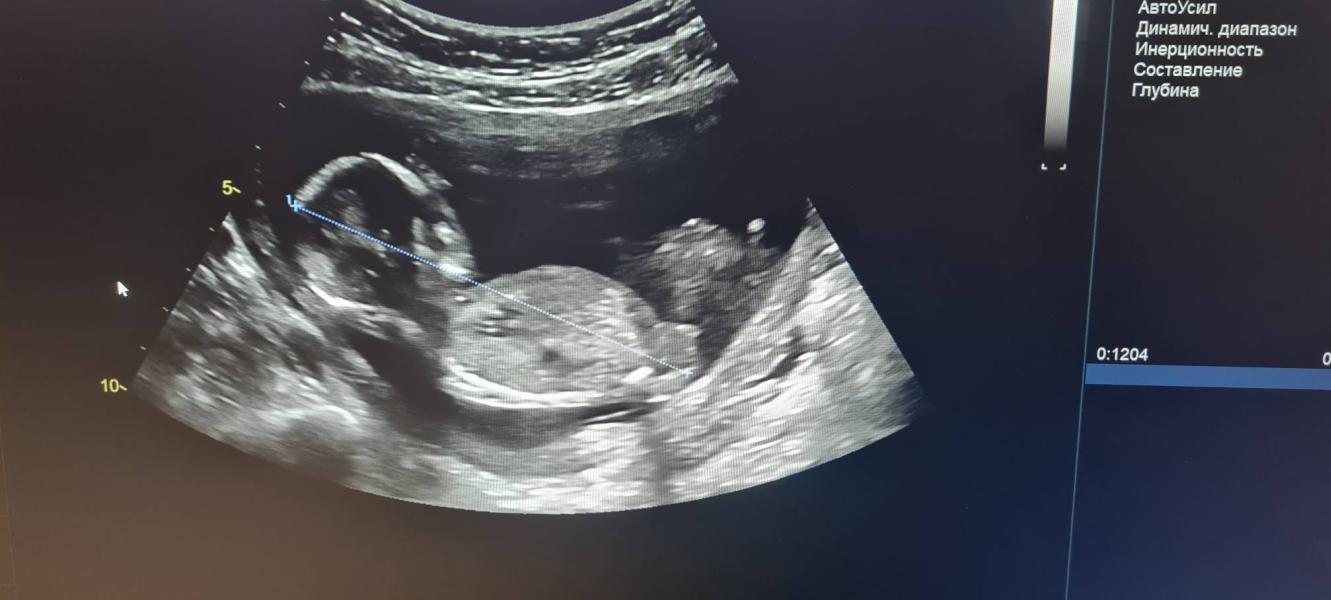

Вот такой уже карапуз, делали узи 4 дня назад. Вроде как мальчик)

по бугорочку похоже на девочку)

Больше на девочку похоже 😄

@madinasamoshina, у девочек продолжение позвоночника, а у мальчиков прямо торчит вверх

Я лежала в больнице, и перед выпиской сделали узи, и там он прям палочкой махал, и узист сказала мальчик